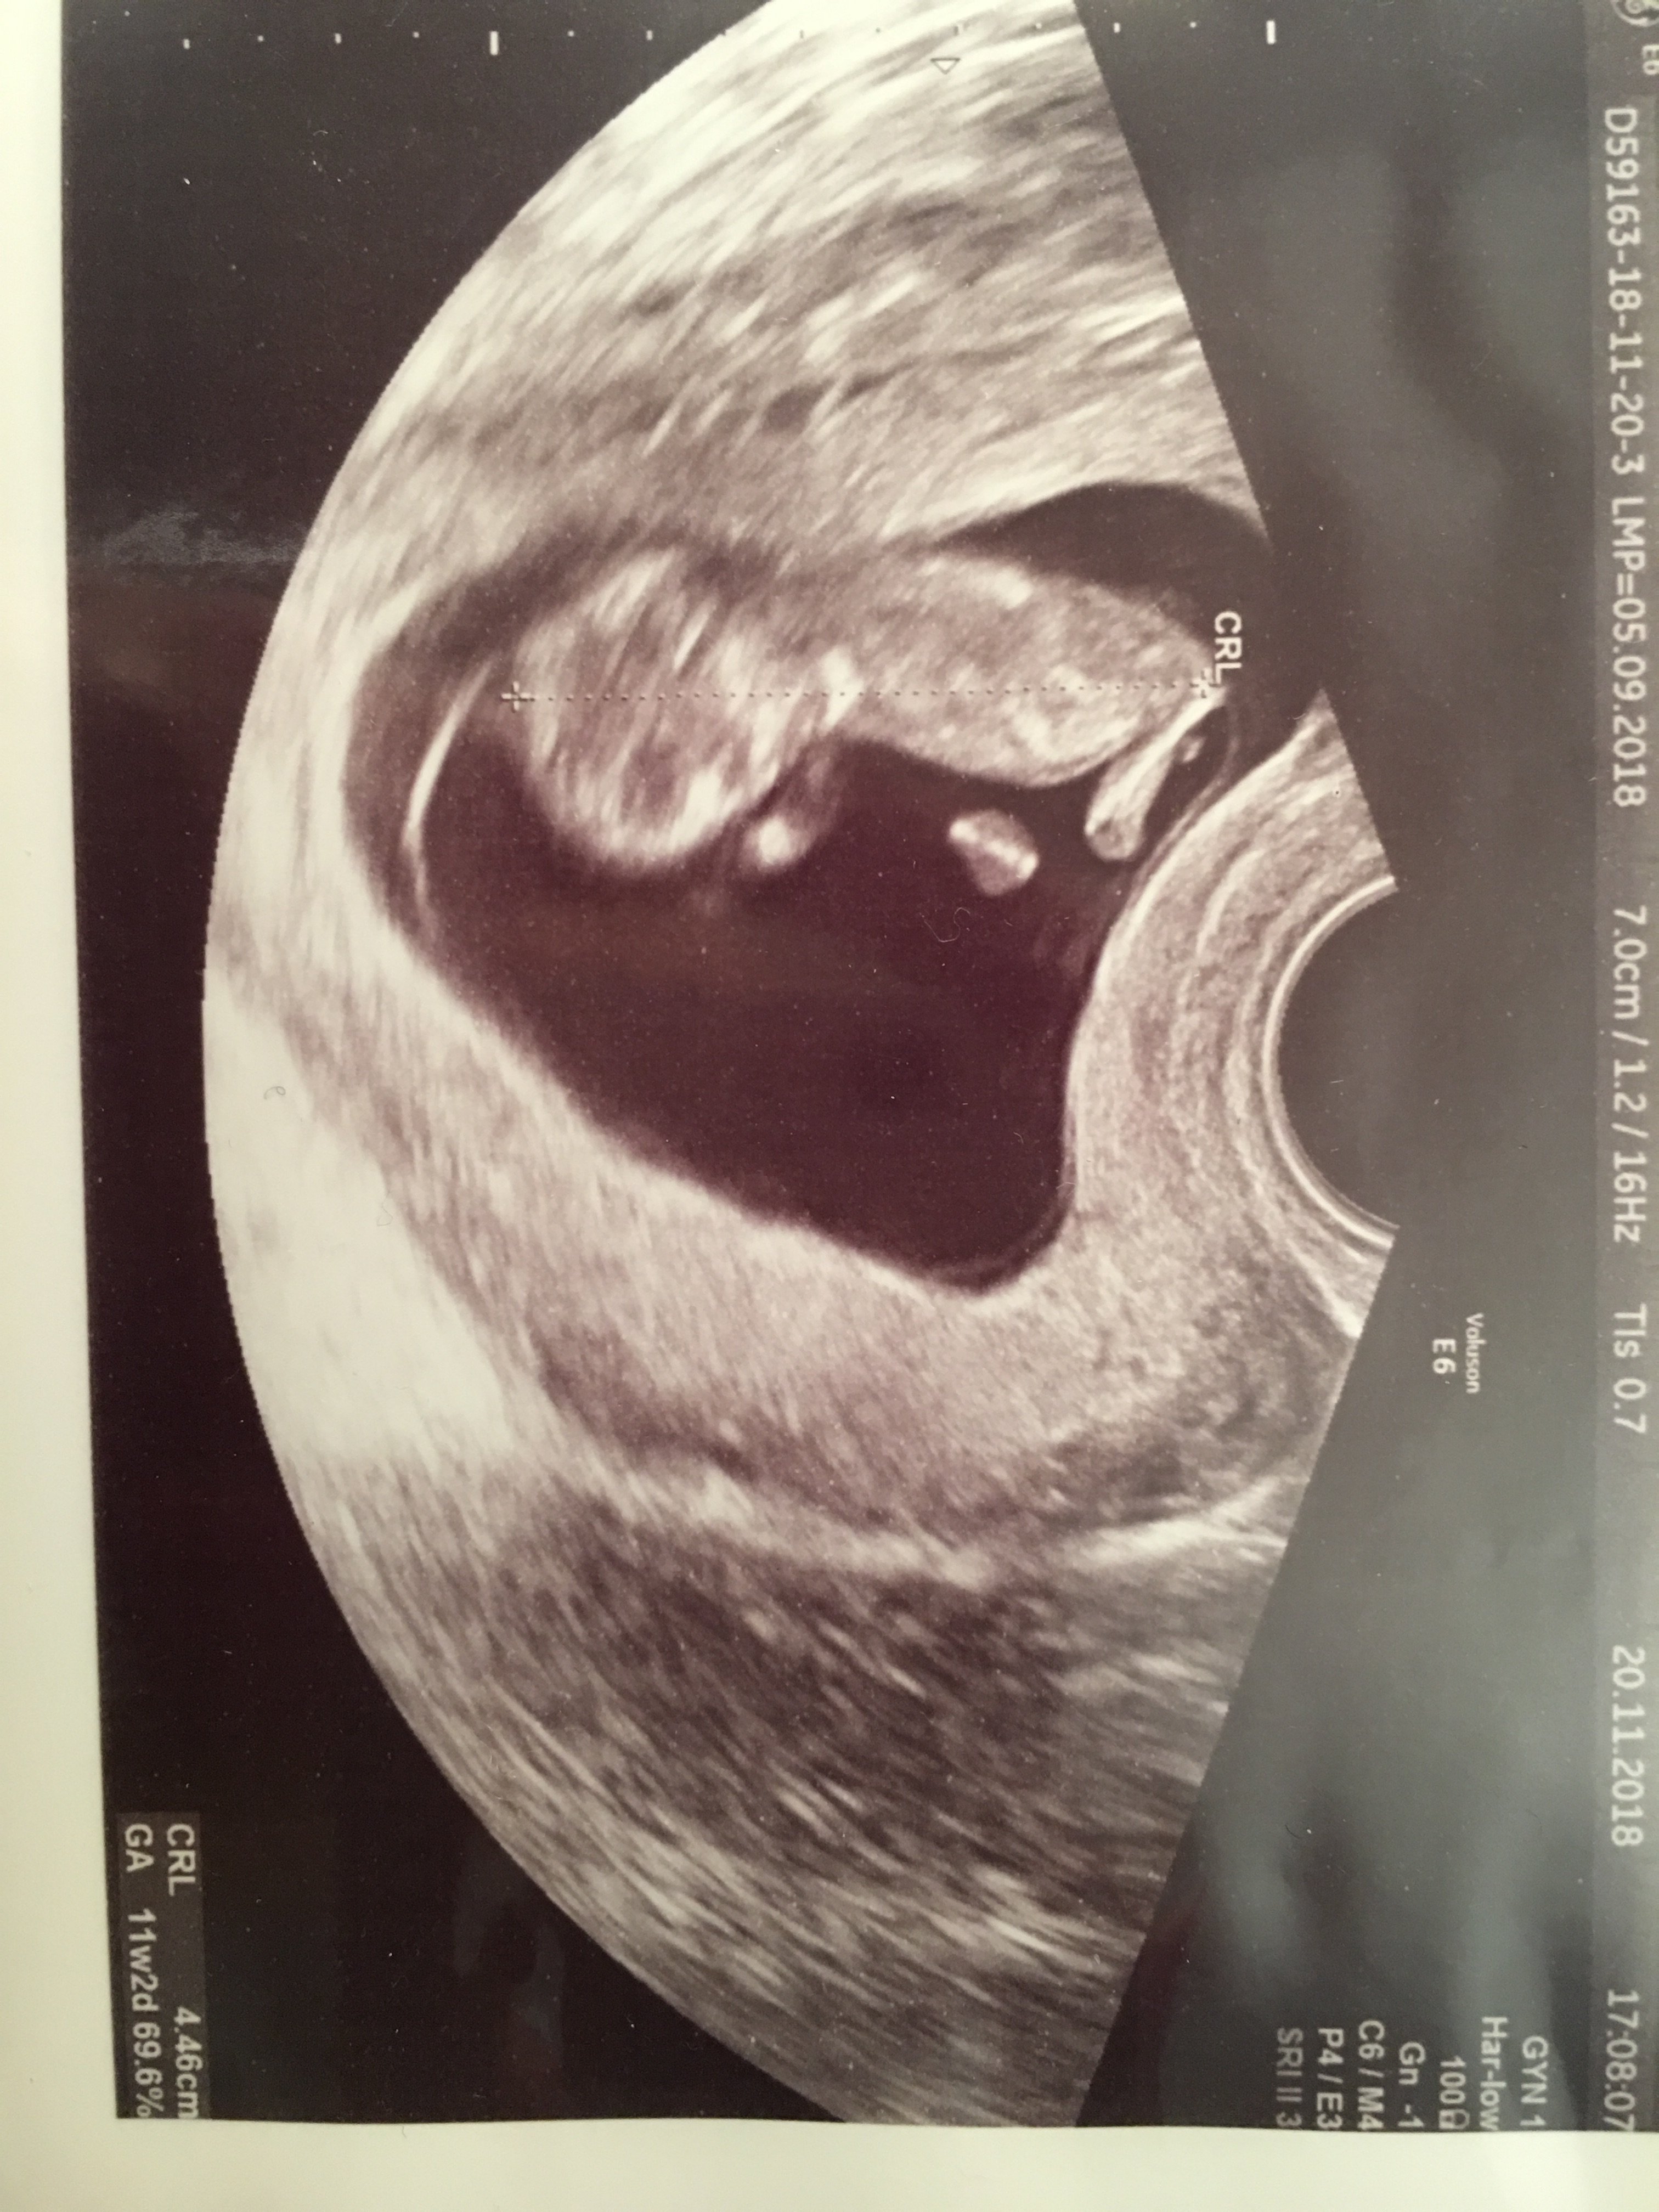

Melduje się po wizycie :)

Dzieciątko się tak wierciło ze nie mógł doktor wymierzyć :) po kilku próbach mamy 4,46 cm :)

Według om dzisiaj jest 10t6d a na usg mamy 11t2d

W załączniku zdjęcie po dzisiejszym usg :)

Łezka poleciała :) ostatnie usg miałam 4 tygodnie temu to widziałam kropeczke z bijącym serduszkiem, a dzisiaj pierwszy raz słyszałam i do tego taki mini człowieczek :) chwale się moja największa miłością ;D